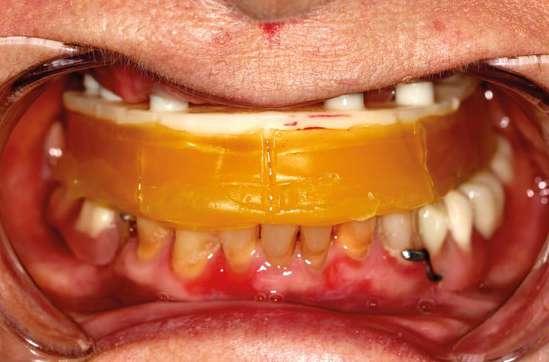

Se monitorizó la evolución de la cicatrización durante las semanas siguientes y se fue adaptando la prótesis provisional a los cambios gingivales mediante silicona de rebase blando. (Ufi Gel SC Voco). Pasados cuatro meses, procedimos a realizar la exposición de los implantes y la conexión de los pilares Multi-unit Xeal™ rotatorios mediante un protocolo One abutment- One time. Durante la segunda cirugía, nos aseguramos de dejar un tejido blando de suficiente grosor y altura de encía queratinizada que nos garantice un mantenimiento del hueso crestal. Se seleccionaron las alturas y angulaciones de estos y se colocaron a 35 Nw de torque. La topografía y las propiedades químicas de estos pilares han sido diseñadas para facilitar la adhesión del tejido blando al pilar y así tener una mejor barrera que proteja el hueso subyacente. Al colocar estos pilares logramos igualar las alturas de las plataformas de los implantes, siendo más cómoda la realización de la prótesis definitiva y también mejorando la higienización de la futura prótesis. (Fig. 12 y 13).

Realizamos un primer escaneado con scan bodys atornillados a los pilares intermedios. Dichos componentes escaneables presentan una geometría retentiva en su cuerpo que nos permite ferulizarlos entre sí, consiguiendo un flujo de escaneado continuo que mejora la repetibilidad y disminuye la deformación de los escaneados, facilitando alcanzar la pasividad en las rehabilitaciones múltiples.

Se atornillan los scan transfer en boca, verificando el ajuste y se realiza un primer escaneado sin ferulizar. A continuación, se recomienda ferulizarlos entre sí en boca con resina auto y se realiza un segundo escaneado.

No obstante, para asegurarnos de un ajuste pasivo óptimo que evite complicaciones mecánicas y biológicas hicimos una segunda comprobación para lo que usamos una ferulización mediante una estructura de acero inoxidable fresada y diseñada de forma digital con un software CAD. Esta técnica expuesta por Revilla-Leon et al. integra los procedi-

mientos analógicos y digitales y nos permite tener un mayor control al calcular y diseñar exactamente los agujeros para desatornillar los aditamentos de los implantes, así como el espacio para el material de impresión; además la cubeta tiene una única posición lo que simplifica enormemente el procedimiento. (Fig. 14, 15 y 16).

Para poder evaluar la oclusión, estética, dimensión vertical, sellado gingival, etc., usamos pruebas plásticas impresas en 3D diseñadas en Exocad. Sobre éstas hacemos todos los retoques necesarios y una vez controlados, se retornan o se re-escanean para que el laboratorio copie la prueba en resina en la prótesis final. Esto nos permite eliminar el ajuste final en boca del paciente, evitando tener que hacer retoques que provoquen la pérdida de anatomía, así como la generación de superficies abrasivas en las prótesis una vez fabricadas y también evitamos los procedimientos de repulido, que a menudo resultan insatisfactorios. (Fig 17 y 18).